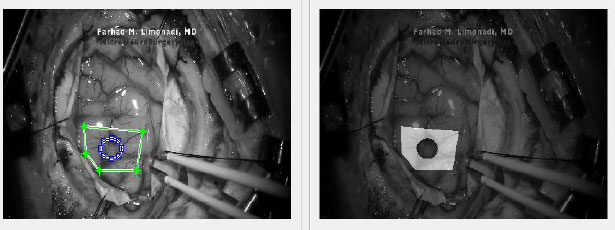

In addition, the reference image for the Metastatic Tumor [8] dataset is shown in Fig. (1). However, reflected glare from the surface of the brain presented a problem regarding the accuracy of the DIC calculations. This was alleviated by carefully placing “seeds” which are selected points that create checks for accuracy.

Additionally, the blue surgical clamps, seen on the right side of the image, also provided a reference that was used to translate the surface displacement unit from pixels to millimeters for each video. It should be noted that the resolution of YouTube JPEG videos is 1920 x 1080 pixels.

After the remainder of the frames were uploaded into Ncorr, a ROI had to be selected for analysis.

Selecting a single and relatively small ROI reduces the computation load by restricting the area of analysis. Furthermore, a smaller ROI increases specificity and can allow for comparisons between different regions. As demonstrated in Fig. (2), Ncorr also allows for the creation of polygonal or elliptical ROIs. Moreover, ROIs can also be “subtracted” to allow for greater precision or to eliminate regions that Ncorr is unable to process.